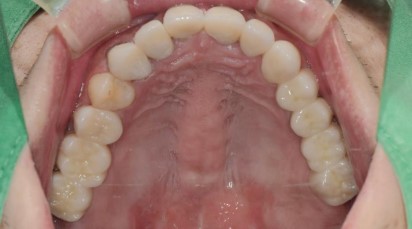

治療前:前牙蛀洞大,牙齦發炎,殘根,小臼齒蛀牙深,牙齒變色。

術前術後口內模擬打好地基->牙周以及根管治療

製作假牙之前,需要先處理:

- 將殘根+智齒拔除

- 牙周治療(也需患者配合良好的刷牙習慣)

- 根管治療